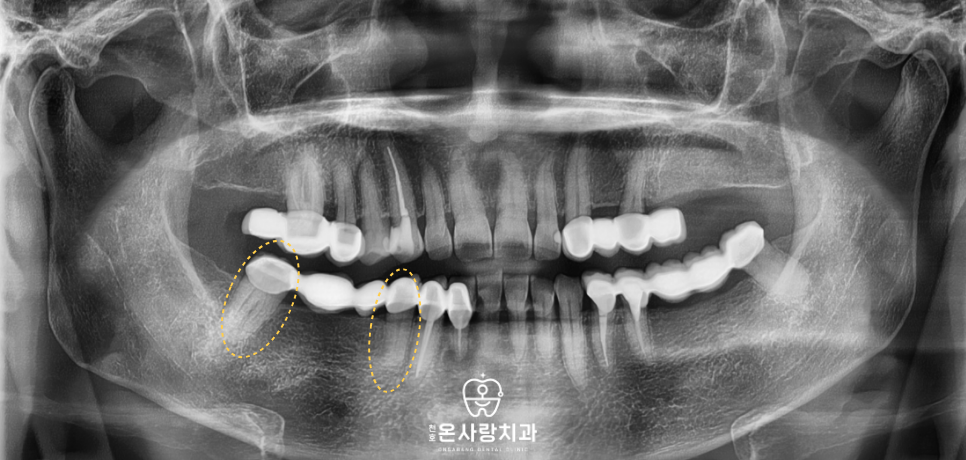

천호온사랑치과를 방문하신 환자분 역시

하악 우측 부위의 모든 치아가

브릿지로 길게 연결되어 있는 상태였습니다.

평소 식사를 할 때 전반적으로

치아에 힘이 실리지 않고

어딘가 모르게 불편함이

지속된다는 점을 호소하셨습니다.

의료진이 정밀한 진단을 통해 살펴본 결과

하악 우측 치아가 하나로 묶여 있는

브릿지 상태였으며 중간에는 2개 치아가

없는 자리를 보철물이 대신하고 있었습니다.

문제는 브릿지를 지탱하고 있는

기둥 치아들의 상태가

제각각이었다는 점입니다.

어떤 치아는 여전히 튼튼했지만

어떤 치아는 내부 손상이 진행되어

더 이상 기둥 역할을 수행하기

어려운 상황이었습니다.